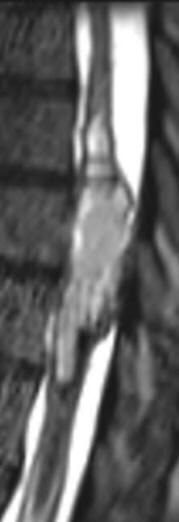

MRI in coronal and sagittal sections showing the tumor before surgery

Intraoperative MRI Sagittal showing radical removal of the tumor.

Intraoperative MRI axial views showing that the spinal cord mass was mainly in the left side supporting the fibertraking data.